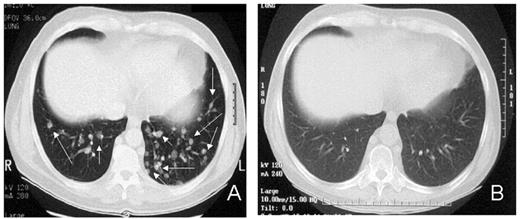

RCC was quickly identified as a target for a GVT effect.31 Ten of the first 19 patients had disease responses including 7 partial and 3 complete responses.32 The first patient treated remains without evidence of disease 5½ years after transplantation (Figure 9 ). Remarkably, all responding patients had failed prior treatment with cytokine-based therapy. Disease responses occurred mostly commonly in patients with pulmonary-restricted metastatic disease, although regression of bulky tumors in multiple metastatic locations has occasionally been observed. Disease responses were typically delayed, occurring 4 or more months after the transplant only after T-cell chimerism had converted from mixed to full donor in origin. Representative lineage, specific engraftment profiles, and their relationship to clinical outcome are shown in 2 patients who underwent nonmyeloablative transplantation and had graft-versus-RCC effects (Figure 10 ). Although GVHD was favorably associated with a disease response (Figure 11 ), some patients had dramatic regression of metastatic disease without having acute or chronic GVHD. Disease progression in the first few months after the transplant did not necessarily preclude a GVT effect; a unique pattern of tumor growth followed by subsequent disease stabilization or regression was observed in several patients. Furthermore, some patients who did not respond to cyclosporine withdrawal had tumor shrinkage after a donor lymphocyte infusion or following treatment with low-dose subcutaneous interferon-alpha.

Advances in understanding the tumor targets and effector populations responsible for GVT effects in RCC are necessary for the development of more effective transplant approaches. Disease regression associated with cyclosporine withdrawal, full donor T cell chimerism, and GVHD all provide strong indirect evidence that donor T cells play an important role in these responses. The observation that tumor regression can occur with or without acute GVHD suggests that both broadly expressed minor histocompatibility antigens, as well as antigens that are restricted to the tumor, are potential targets for allogeneic immune effectors. Preliminary in vitro data have shown that RCC cells express a broad range of mHa that could render them susceptible to a GVT effect in the setting of GVHD.38,39 Along these lines, T-cell clones that kill both patient RCC and hematopoetic cells have been isolated from responding patients.40,41 Furthermore, in a few patients without GVHD, MHC class I restricted T-cell lines with tumor-specific cytotoxicity have been expanded in vitro from the patient’s blood at the time of tumor regression (Figure 12; see Appendix, page 605). Studies to identify potential RCC-restricted antigens using these allogeneic T-cell populations are being pursued. These preliminary findings suggest that distinct T cell populations recognizing tumor restricted antigens and/or antigens shared by both the tumor and normal tissues (i.e., mHa) may be involved in these GVT effects.